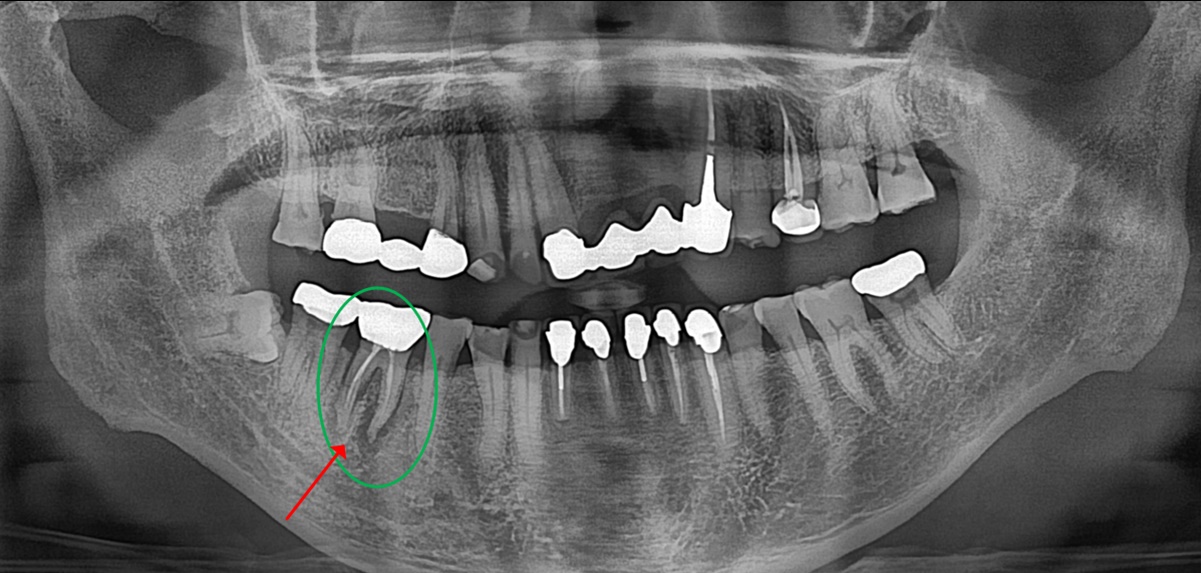

치료 전 파노라마

실제 환자분들은 치아에 문제가 있는지 모르는 경우가 굉장히 많습니다.

치과 정기 검진에서 문제가 있다고 해도 당장 불편한 증상이 없으면 더 사용하기를 원합니다.

음식물 저작시 통증이 지속되고, 잇몸에서 피나 고름이 나면서 부어오르면 그제서야 치과를 내원하시는데요.

위의 사례분의 사진도 보시면 통증이 없었기 때문에 방치하고 계시다가 잇몸이 붓고 아파서 내원 하셨습니다.

엑스레이상 #46 치아 주위 치조골은 모두 소실되었고 즉시 임플란트 치료를 하기에도 곤란한 상태였습니다.